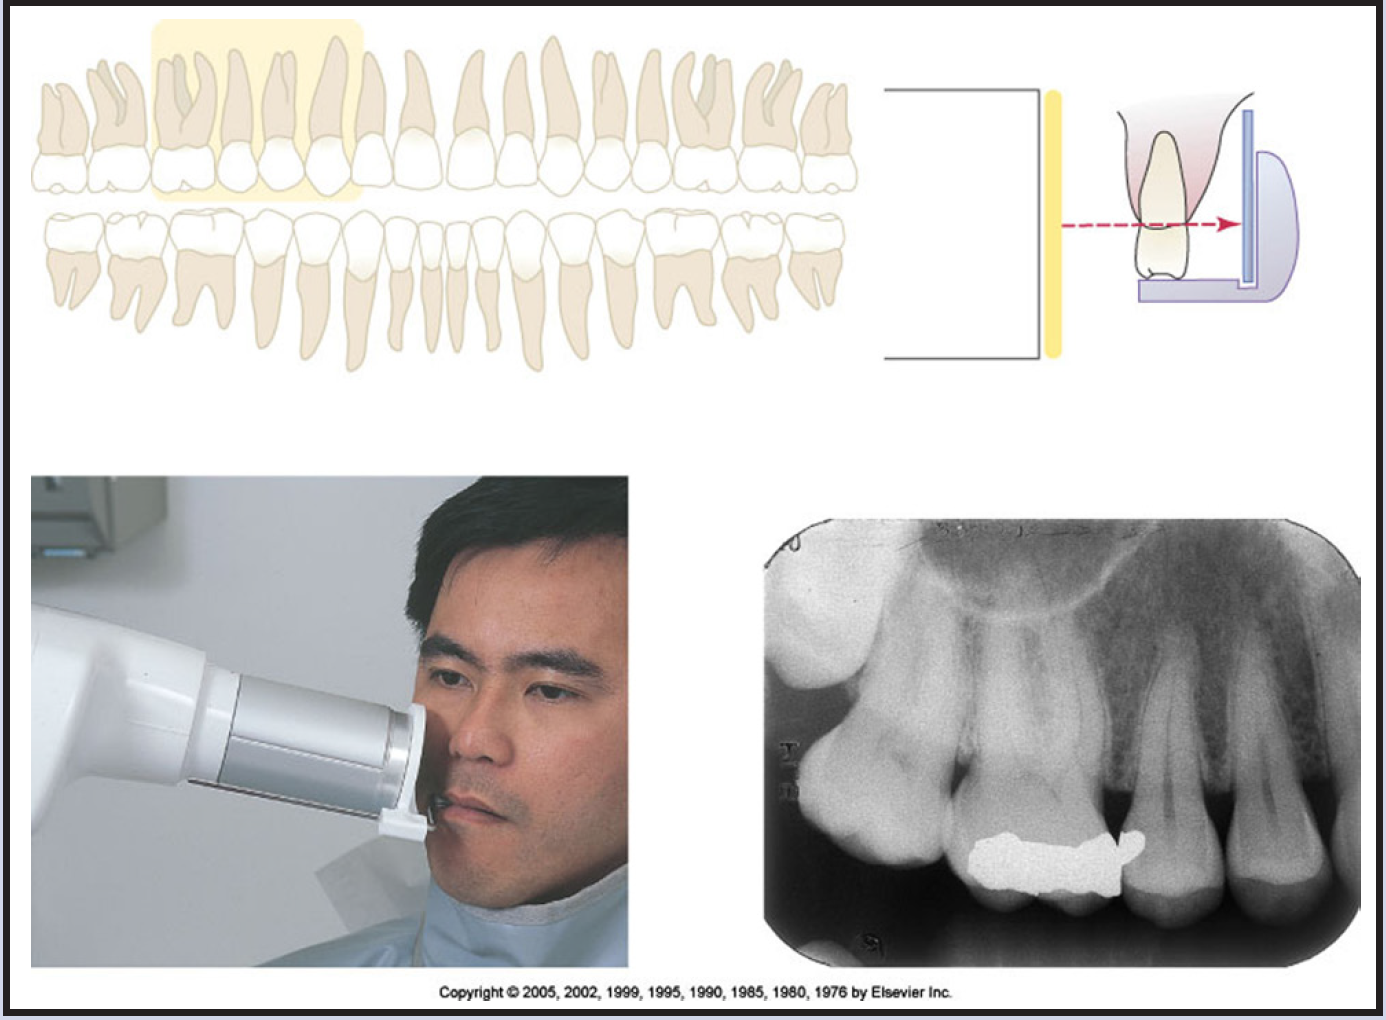

Bitewing images are parallel images because the receptor is positioned parallel to the long axis of the teeth and the beam is perpendicular to the receptor as in Figure 60. A bitewing tab is utilized to stabilize the receptor as the patient bites together.

Tube head position is illustrated in Figure 62, and a sample set of bitewing radiographic images is illustrated in Figure 63.

The interproximal examination may be done using a special type 3 bitewing receptor but is preferably achieved by using four type 2 receptors fitted with a tab. There are also receptor holding devices available that support the receptor as well as provide an external reference for positioning the tube head. The patient stabilizes the receptor by gently biting together on the manufactured tab or on the holding device.